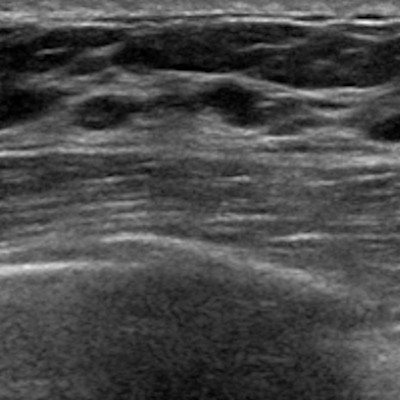

Axial (A) and coronal (B) ABUS images of the right breast show 4-mm irregular hypoechoic mass (arrows) at the 11-o’clock position. The background echotexture is heterogeneous. The mass was assessed as BI-RADS category 4. The patient underwent biopsy at a local hospital and subsequent surgical excision. Surgical histopathologic assessment revealed a 6-mm grade 2 invasive ductal carcinoma without axillary lymph node metastasis; the cancer was estrogen receptor positive, progesterone receptor positive, and HER2 negative. The case is consistent with cancer detected by ABUS screening.ARRS